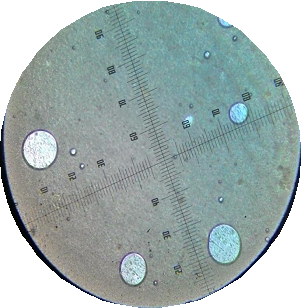

Average globular diameter test

The average globular diameter was measured by the polarizing microscope, which equipped with a calibrated ocular lens and micrometre. The double emulsion was placed on the object glass and covered with glass. Then it was observed using a microscope at 200 times magnification. The observed images were photographed and measured the globule diameter. The average globule diameter test was performed at weeks 0 and 4 [18].

The measurement of the average globular diameter was to see the droplet stability of a double emulsion of snakehead fish powder as shown in table 5 which performed on the external and internal globules using a microscope with a micrometer at 200 times magnification.

| 4 | 8.90±2.45 | 6.01±0.57 | 6.35±1.76 | 4.72±2.57 |

According to Fatimah stated that oil-in-water emulsions (secondary) can be formed when using surfactants with high HLB values such as Tween 80 (HLB 15). Meanwhile, in her study comparing the use of Tween 80 with a concentration of 0.5%, 1% and 1.5% w/v, it was found that the use of Tween 80 at a concentration of 0.5% and 1% had not been able to form an o/w type emulsion (secondary). While at the concentration of 1.5% formed emulsion type o/w (secondary) with the size of globular diameter 1-5 μm. This is related to the obtained results, which indicates that the higher Tween 80 concentration used (F4) in the o/w type secondary emotion, the greater average globular diameter as shown in fig. 5. However, the average globular diameter decreased during the week 4. This corresponds to the double emulsion instability of coalescence between the inner and outer liquid phases marked by a decrease in the average size of the globular diameter of formula [16].

A B

C D

Fig. 5: The picture of globular diameter each formula the week 4, (A): a droplet of F1; (B): F2; (C): F3; (D): F4